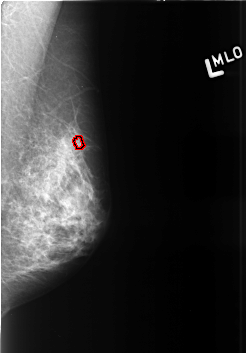

B_3426_1.LEFT_MLO

LEFT_MLO LINES 4232 PIXELS_PER_LINE 2944 BITS_PER_PIXEL 12 RESOLUTION 50 OVERLAY

FILE: B_3426_1.LEFT_MLO.OVERLAY

TOTAL_ABNORMALITIES 1

ABNORMALITY 1

LESION_TYPE CALCIFICATION TYPE ROUND_AND_REGULAR-PLEOMORPHIC DISTRIBUTION CLUSTERED

ASSESSMENT 4

SUBTLETY 3

PATHOLOGY BENIGN

TOTAL_OUTLINES 1

BOUNDARY